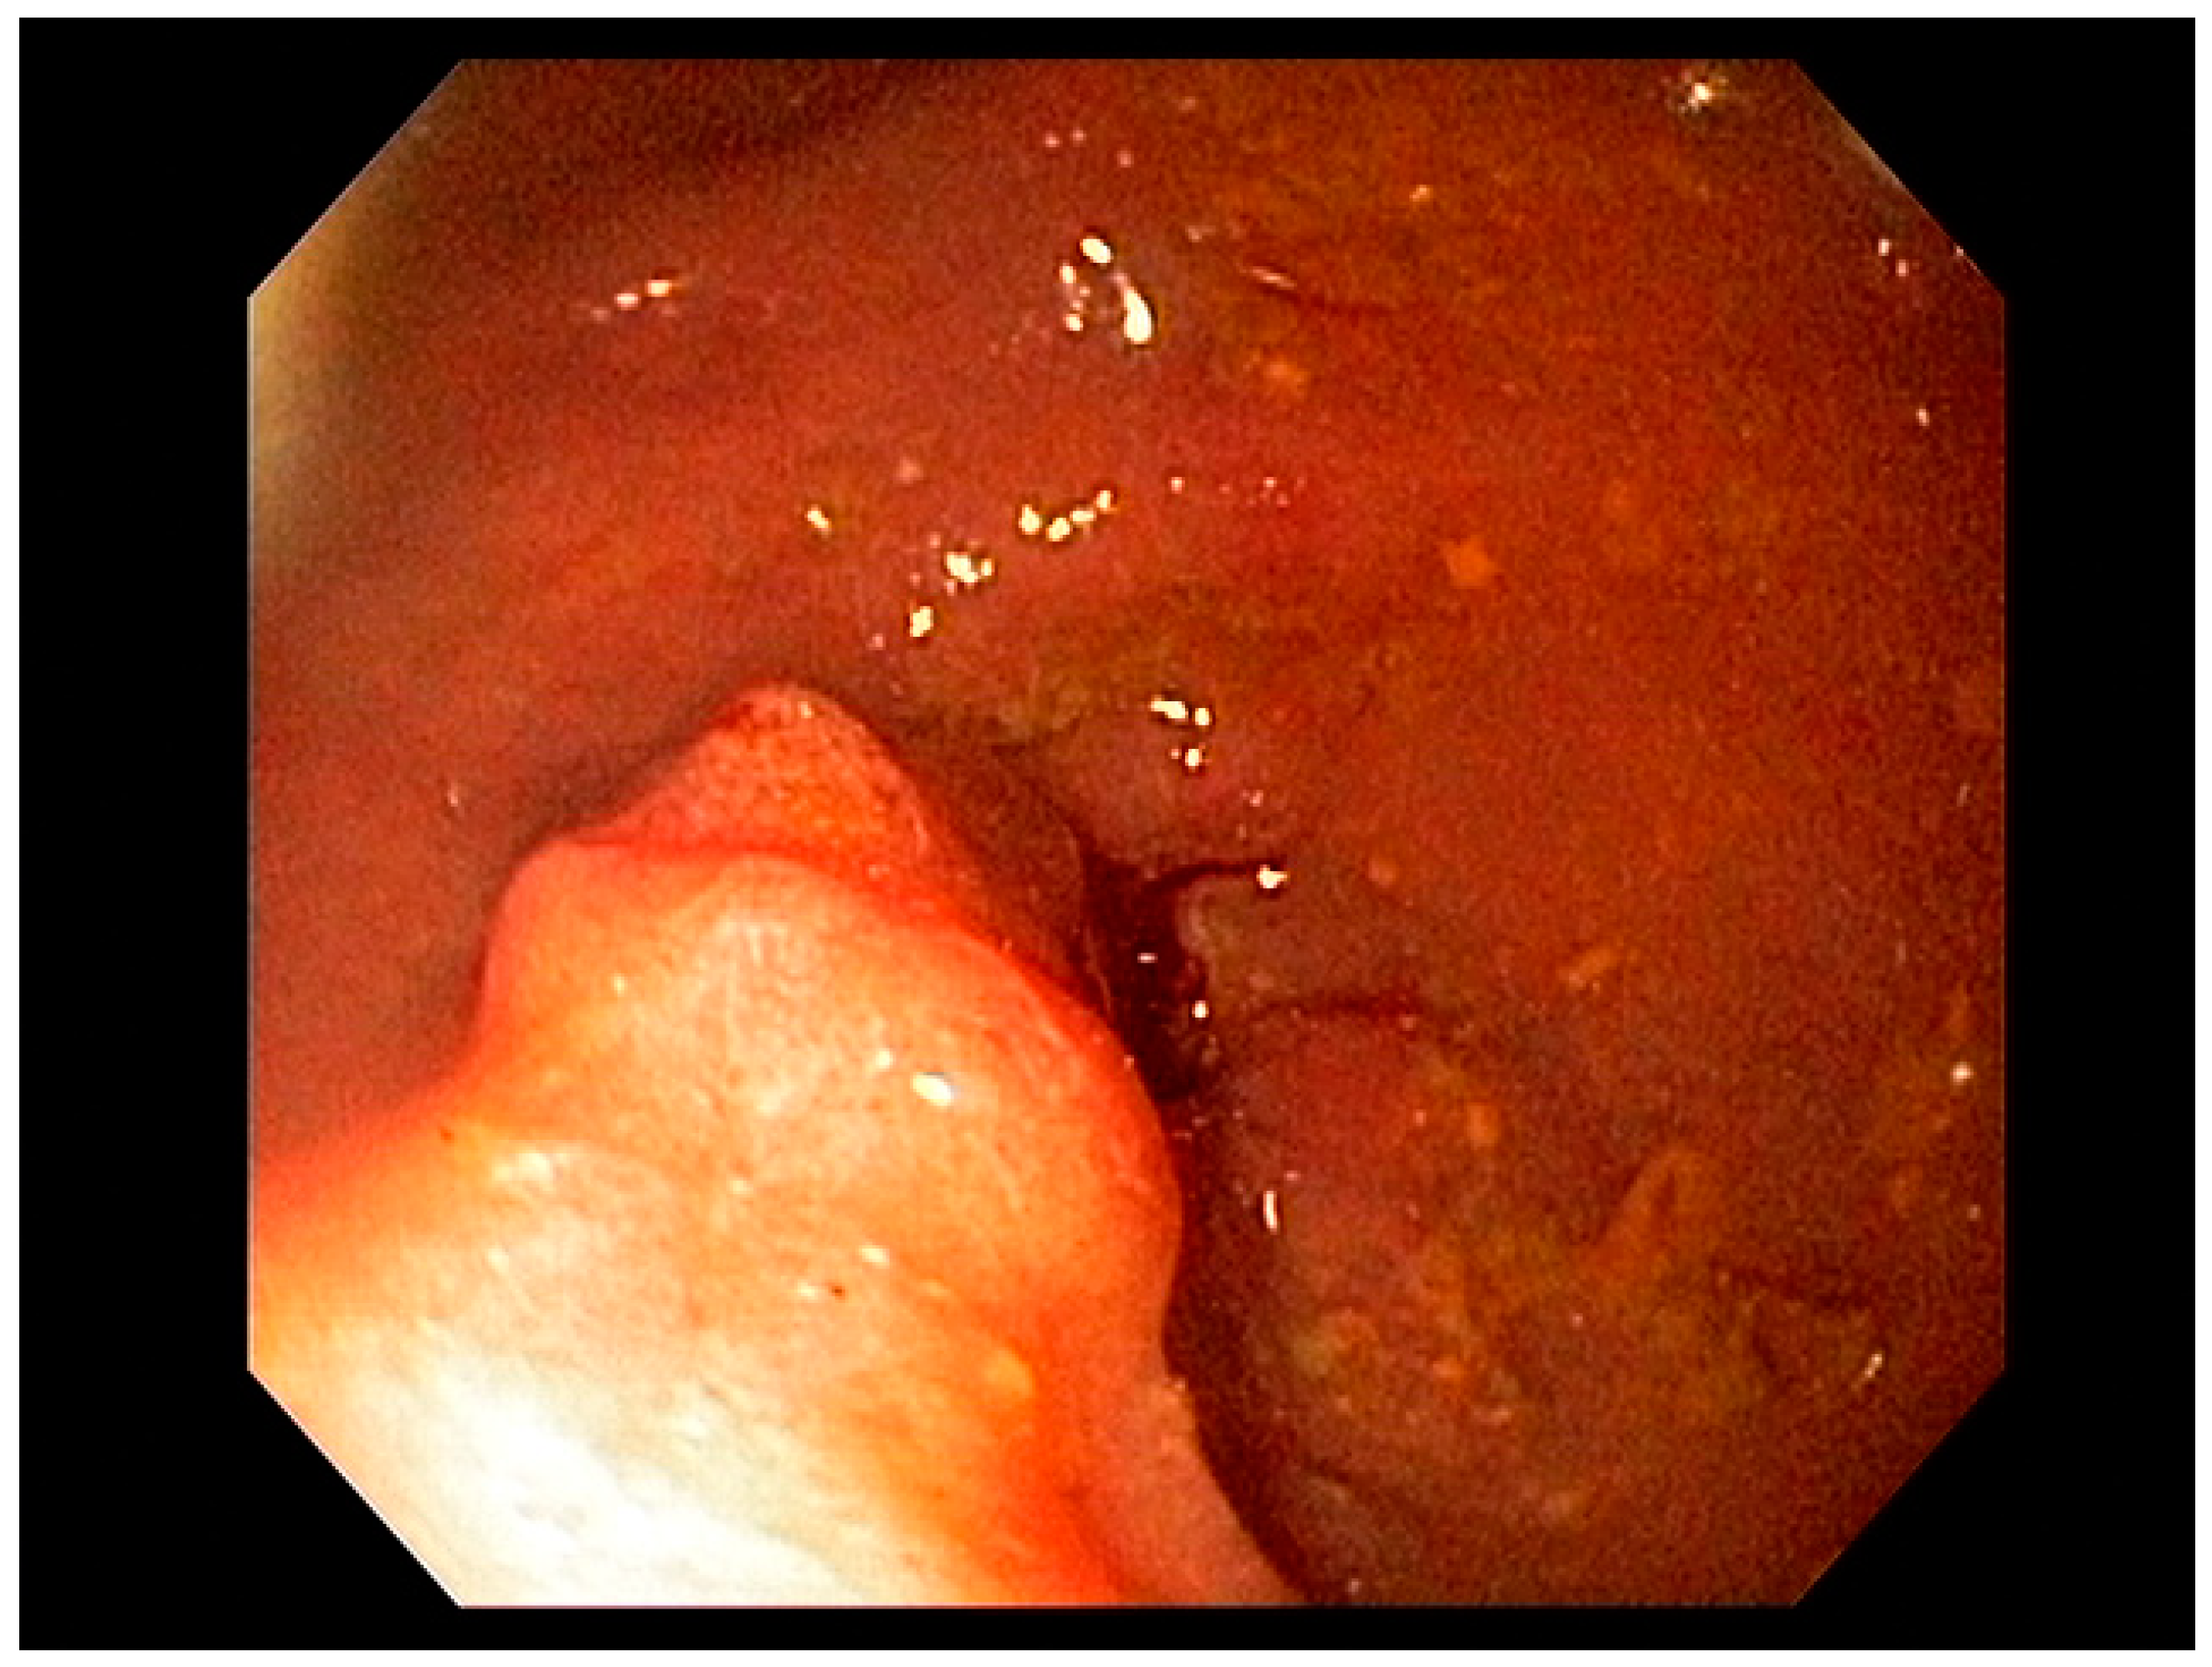

3.2. Endoscopic Resection Techniques for Early-Stage Esophageal Cancer (T1a and T1b)

4.2. Early Gastric Cancer (EGC)

4.3. Endoscopic Ultrasound in Staging of Gastric Cancer